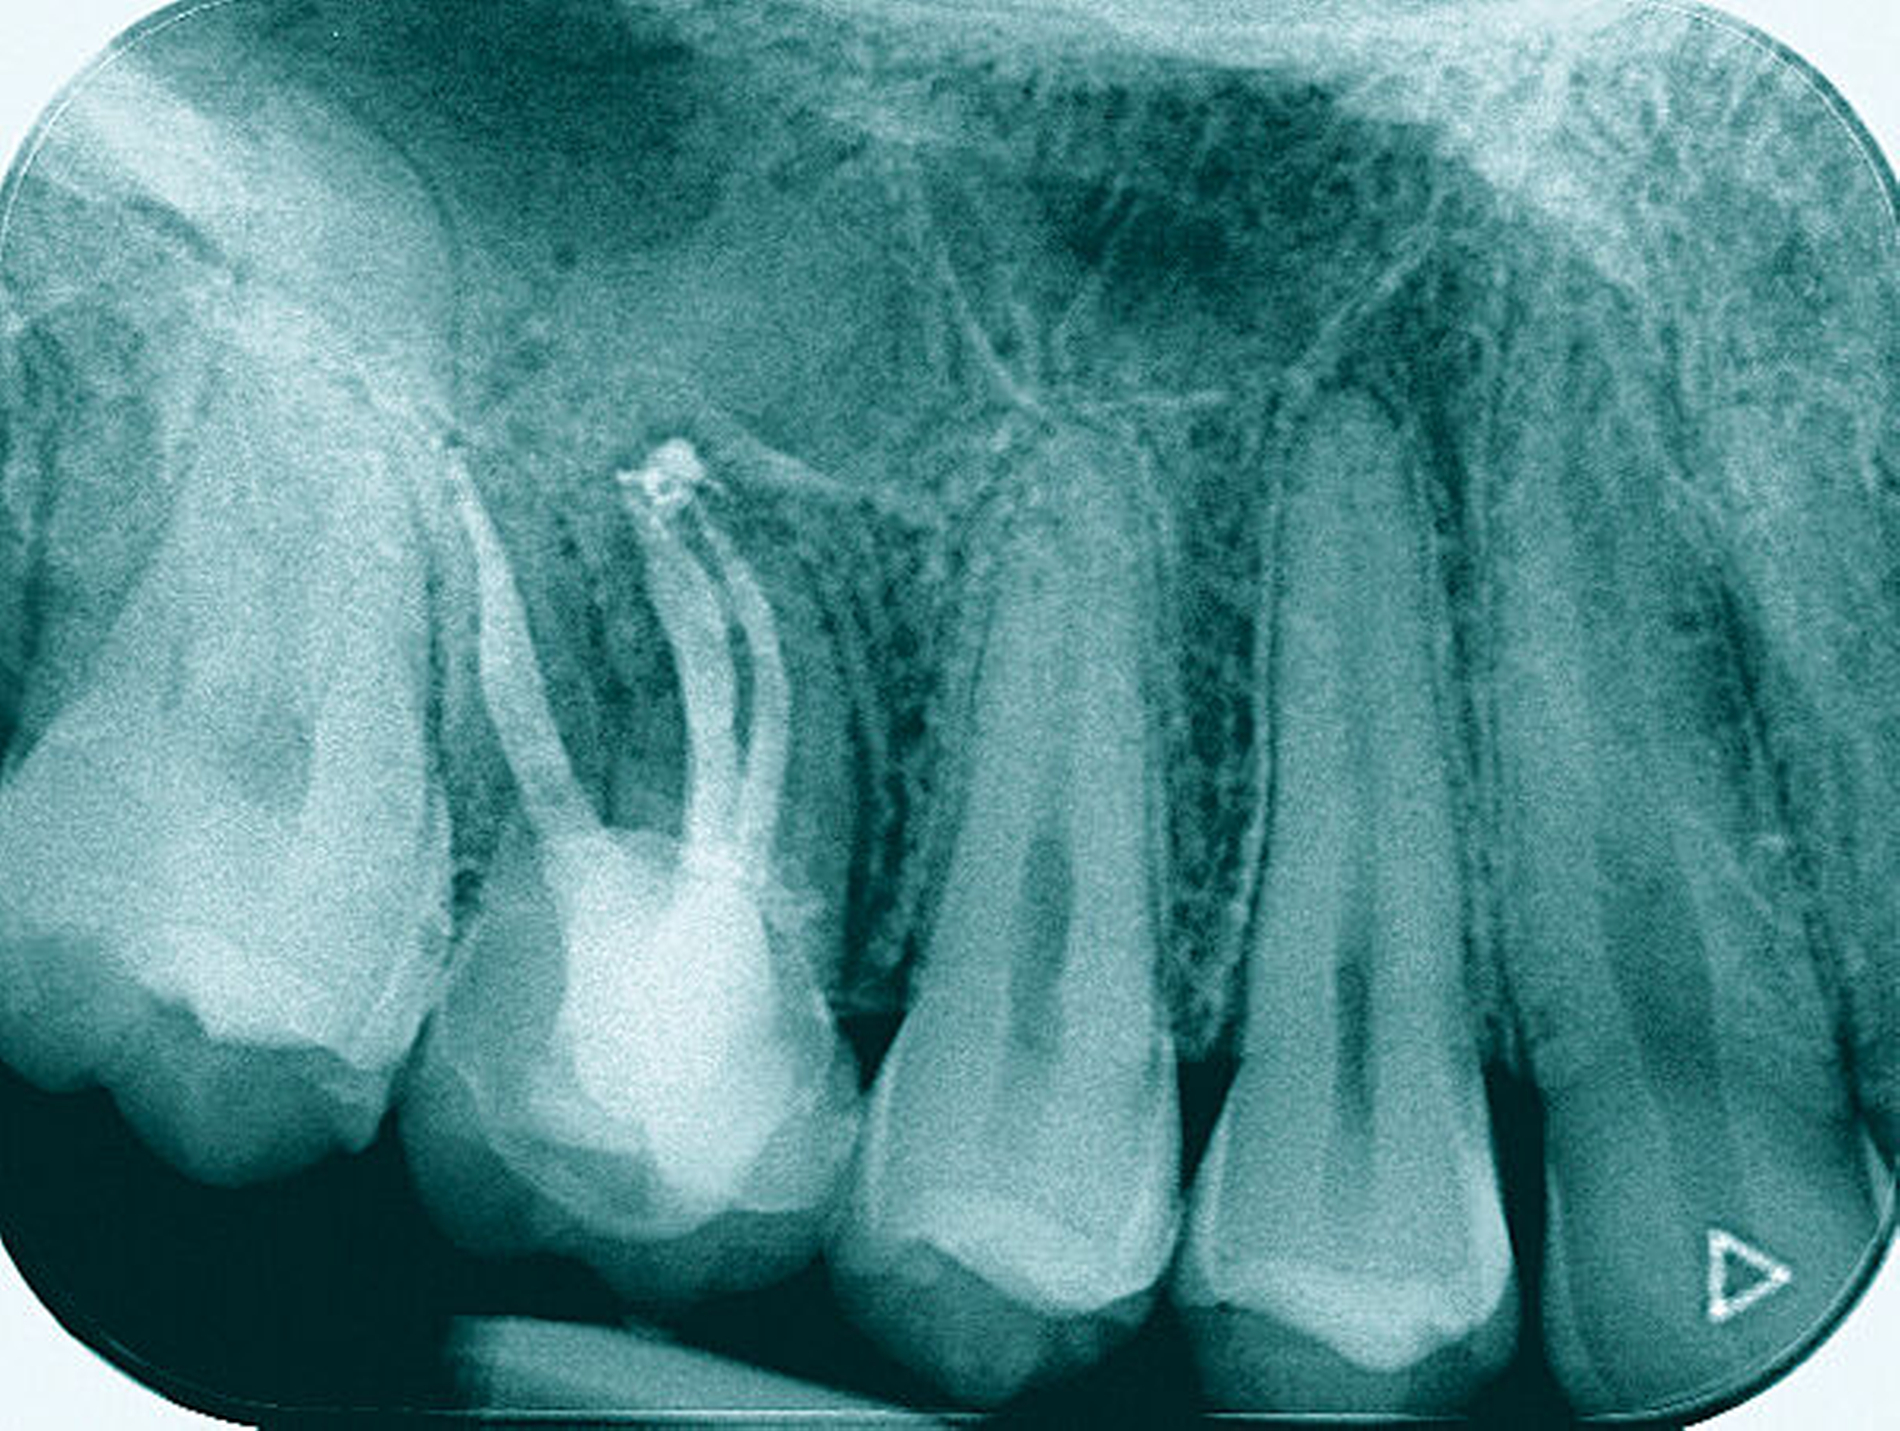

Ein 59-jähriger Patient stellte sich erstmals 2015 mit rezidivierenden pochenden Beschwerden und zeitweise zusätzlich auftretendem Pusaustritt an Zahn 16 vor. Klinisch zeigte sich ein ausgeprägter Attachmentverlust distal mit bis apikal sondierbarer distobukkaler Wurzel, Furkationsbeteiligung und Pusaustritt sowohl über den Parodontalspalt als auch durch einen distobukkal gelegenen Fistelausgang. Zunächst erfolgte die endodontische Behandlung des Zahnes 16 mit anschließender systematischer PA-Therapie. Bei persistierender parodontaler Problematik an 16 wurde die Möglichkeit der Teilamputation der distobukkalen Wurzel mit dem Patienten diskutiert, um die Hygienefähigkeit und damit die Prognose des Zahnes zu verbessern. Auch über die Extraktion als Alternative wurde der Patient aufgeklärt. Er war allerdings motiviert, seinen Zahn so lange wie möglich zu erhalten.

So erfolgte die Amputation der distobukkalen Wurzel mit anschließender Versorgung des Zahnes mittels Vollkrone. Die Situation an 16 ist seitdem für den Patienten subjektiv stabil, die aktuelle Röntgenkontrolle zeigt jedoch eine Progredienz der parodontalen Defekte trotz regelmäßiger UPT und subjektiv guter Mitarbeit des Patienten, was die Prognose des Zahnes negativ beeinflusst. Ursächlich hierfür kann eine persistierende parodontale Infektion durch den trotz Wurzelamputation immer noch schwer für die häusliche Mundhygiene zugänglichen Furkationsbereich mit enger Lagebeziehung der mesiobukkalen und der palatinalen Wurzel sein. Der Patient ist allerdings aktuell mit der Situation zufrieden und beschwerdefrei und wünscht daher noch keine Extraktion des Zahnes, auch wenn diese sich nun fünf Jahre nach dem initialen Befund nicht mehr sehr lange vermeiden lassen wird.